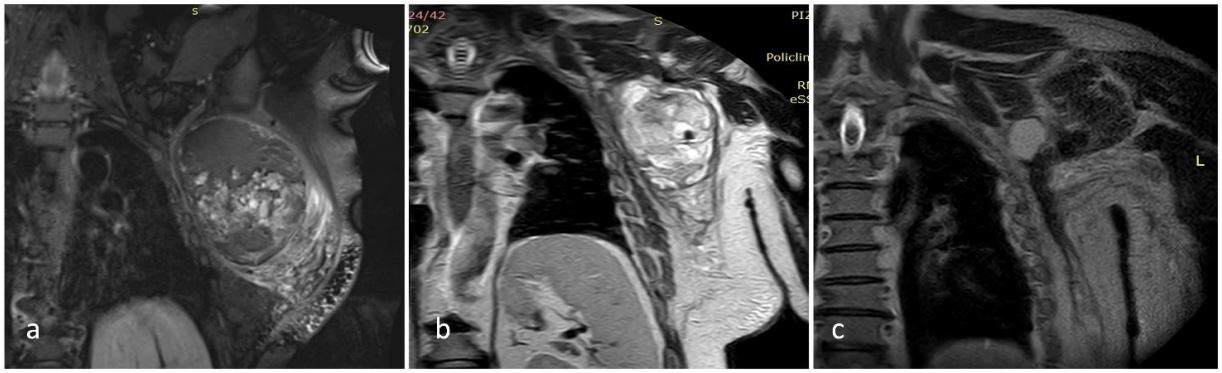

MRI imaging of the mass before and after the preoperative treatments, and following the surgery, is shown in Figure 1.

Figure 1: Pretreatment (a) Post-treatment (b), and Postoperative (c) MRI images: a) September 2021; b) November 2021; c) March 2022.